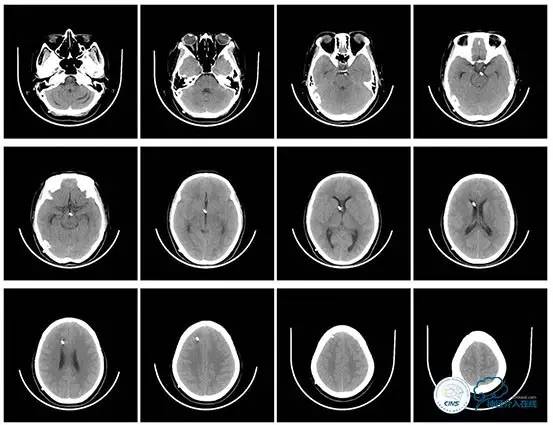

术后即刻患者诉头痛完全缓解。

双眼视力较前有改善。

3天后腰穿:颅内压:75mmH2O,转当地医院眼科继续治疗。

术后头颅CT